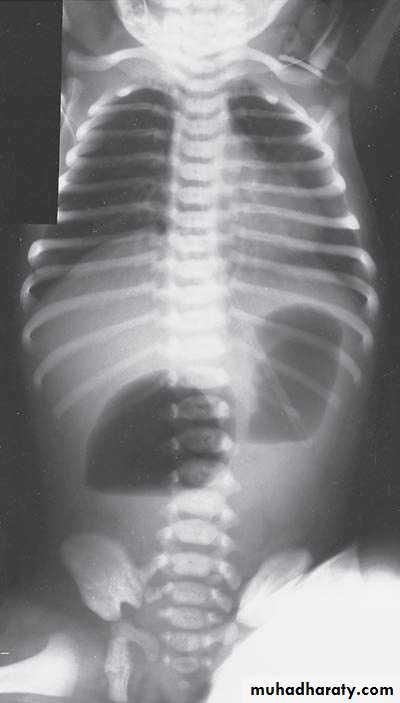

Bowel Obstruction

Diagnosis:

first photo upper bowel obstruction // second photo lower bowel obstructionDescription:

double bubble signCauses of obstruction in the first photo:

1- duodenal obstruction2- duodenal atrasia

3- annular pancreas

4- mal-roation of bowel

Cardinal symptoms of bowel obstruction (first photo):

1- mild abdominal distention (epigastric distention)2- failure if pass of meconium

3- bile stain vomiting

Note:

In pediatric we cannot say small or large bowel obstruction but we say upper

or lower bowel obstruction